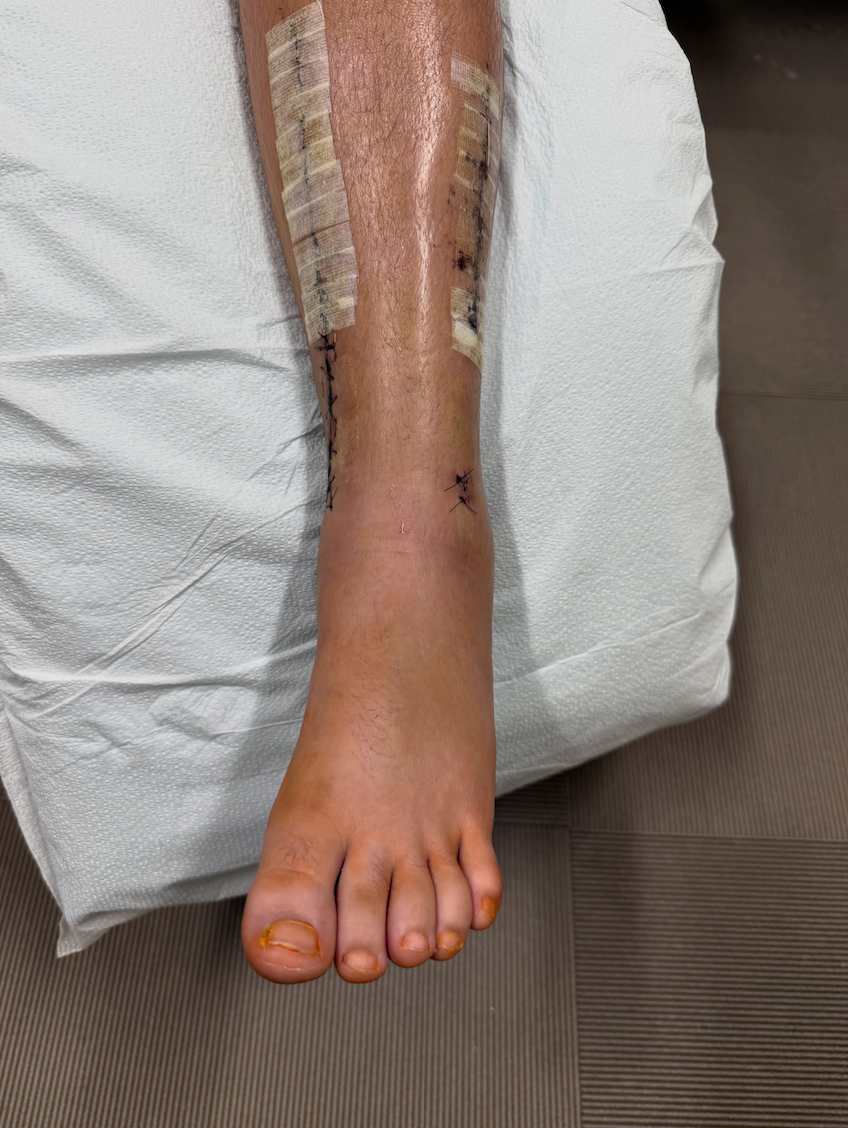

On February 23, Annie’s young daughter, Adelynn, was seriously injured in an accident when another person fell onto her, causing a severe break to her ankle in three places, along with a dislocation and damage to a major artery in her foot which led to compartment syndrome.

What followed was something no family is ever prepared for. Adelynn underwent five surgeries and spent six days in the hospital as doctors worked to stabilize her injury and relieve complications from the trauma.

Thankfully, she has now made it out of the most critical stage and has been placed in a hard cast. She is finally on the path toward healing—but the road ahead will be long.